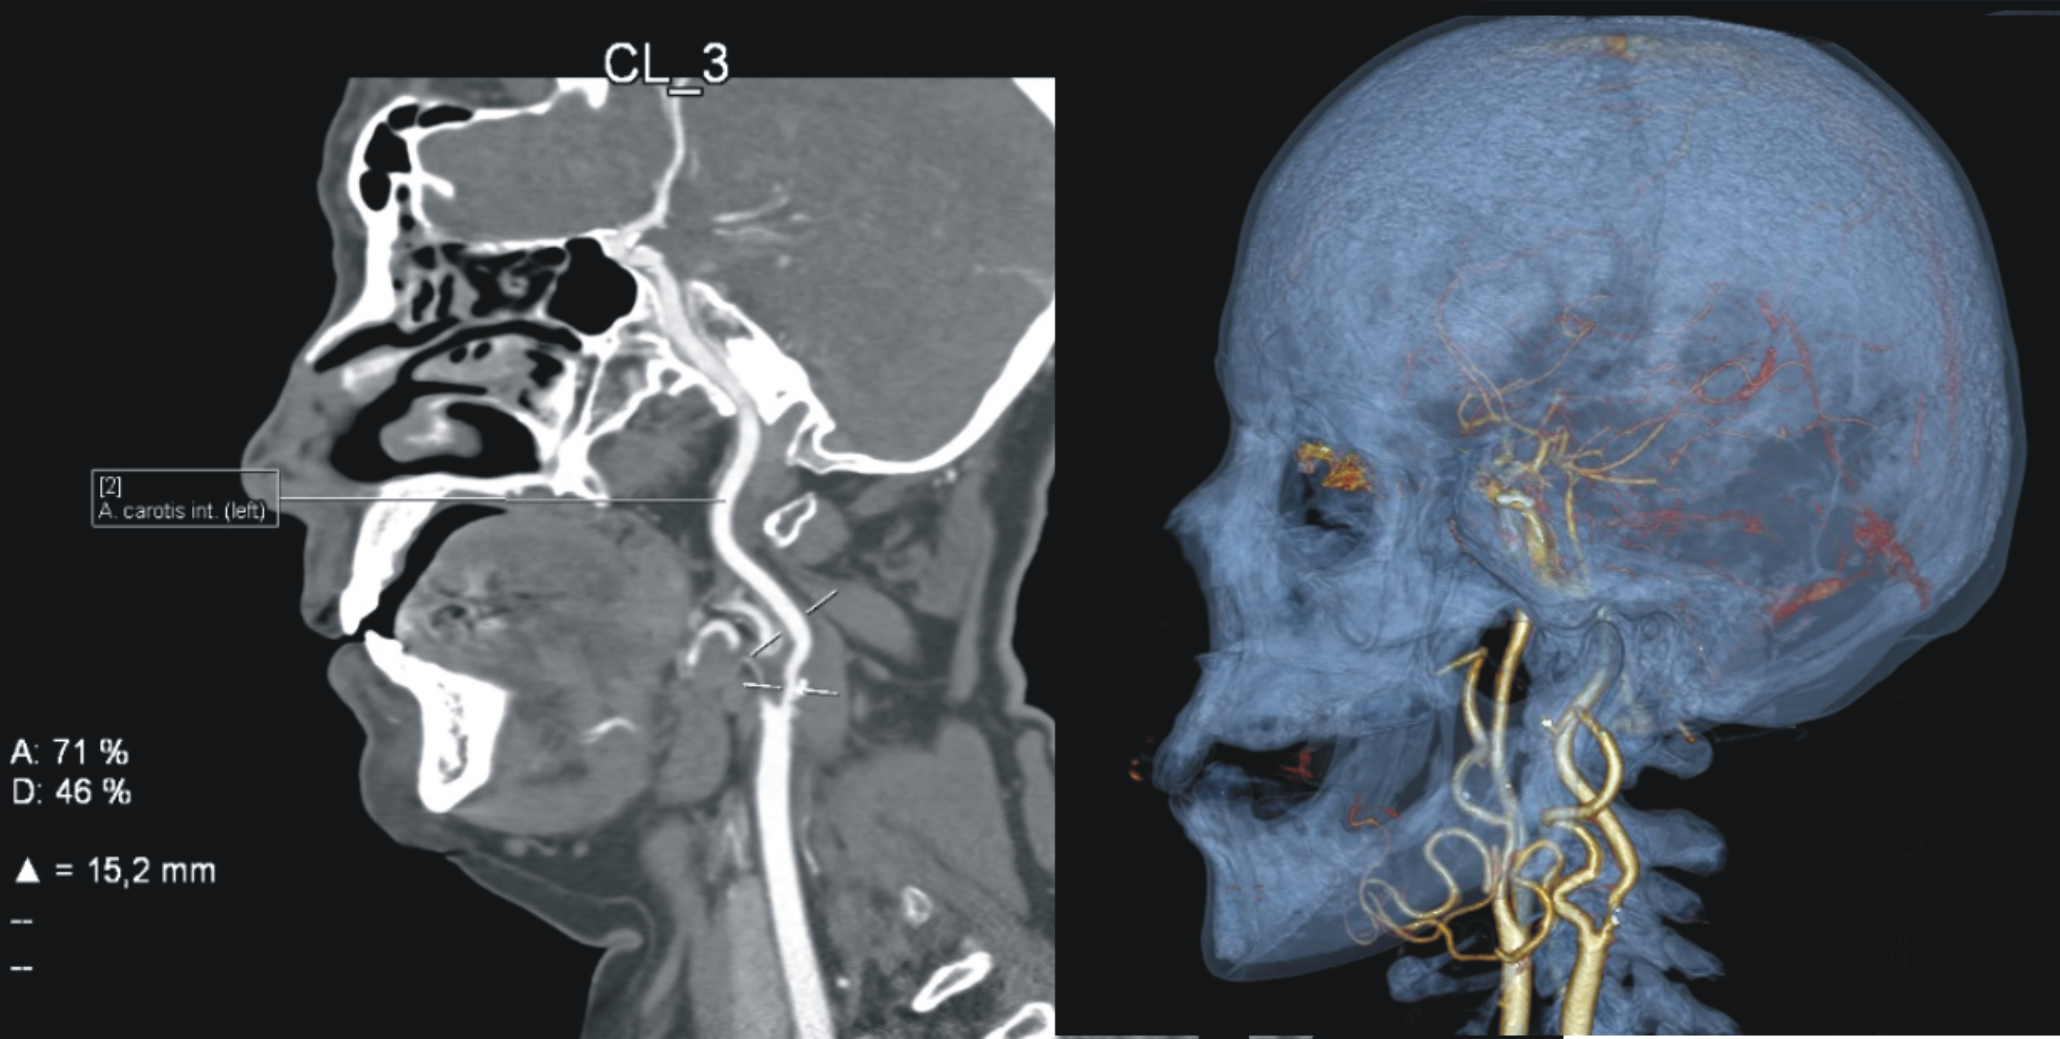

21.01.2022 выполнена каротидная эндартерэктомия слева. Операция выполнялась под эндотрахеальным наркозом с непрерывным нейромониторингом методом церебральной оксиметрии в ближнем инфракрасном диапазоне. Использовалась классическая методика с линейной артериотомией общей и внутренней сонной артерии, открытой эндартерэктомией и пластикой артериотомического дефекта ксеноперикардиальной заплатой шириной 10 мм, длиной 6 см. Время пережатия сонных артерий составило 25 мин. Особенностью операции являлась короткая шея пациентки и высокая бифуркация сонных артерий, тем самым для оптимальной визуализации внутренней сонной артерии была частично выделена поднижнечелюстная слюнная железа (рис. 1).

Рис. 1. МСКТ АГ брахиоцефальных артерий. Высокая бифуркация левой общей сонной артерии. Стеноз левой внутренней сонной артерии 71 % (NASCET)